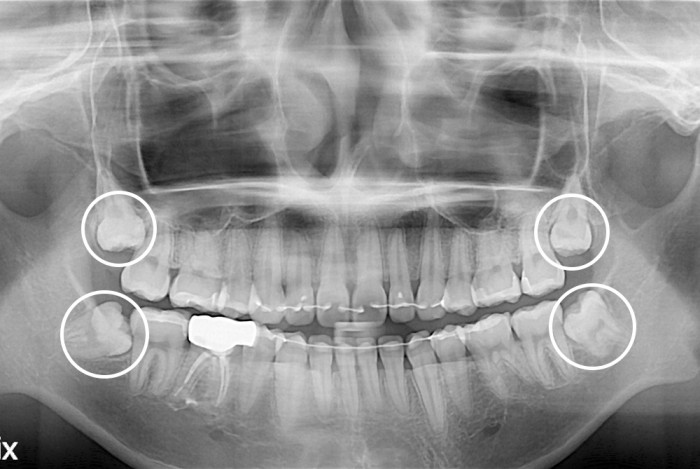

[사랑니] 사랑니

치료전 : 2020-01-22